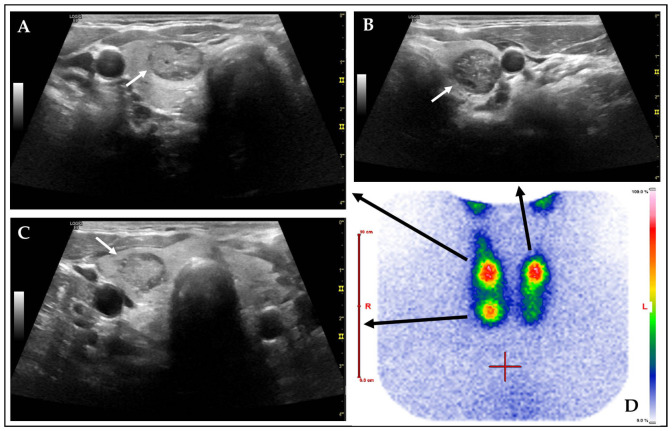

背景/目的:自主功能甲状腺结节(AFTNs)最常被诊断为良性。然而,它们在超声(US)风险分层系统(rss)中显示出很高的评级,该系统利用了传统静态图像捕获(SIC)文档的当前临床标准方法。本研究的目的是评估与SIC相比,cine loop (CL)视频序列的RSS评分和各自的细针细胞学(FNC)推荐值。方法:2015年11月至2023年11月期间,407例424例aftn患者被纳入这项单中心回顾性研究。对记录的US CL和SIC进行病变分析,并比较US特征、Kwak和ACR TIRADS、ACR FNC建议以及评估困难和伪影。采用SPSS软件中的Chi2检验和Spearman相关系数进行统计分析。p值< 0.05为显著性。结果:在比较CL和SIC时,观察到所有US特征、RSS评分和ACR FNC建议之间存在强到非常强的相关性(Spearman相关:各p < 0.001)。对于大约60%的aftn,给予ACR FNC推荐。Kwak TIRADS比ACR评分更符合aftn的良性本质。CL明显比SIC捕获更多的“回声灶”(ch2: p < 0.001)。伪影(图像质量差、声学阴影、矢状面不完全显示AFTN)在CL中更为常见,影响了~40%的AFTN,而在SIC中为~15% (χ 2: p < 0.05)。观察到CL和SIC之间的评估置信度弱相关,SIC优于CL (Spearman相关:各p < 0.001)。结论:在RSS评分和ACR FNC建议方面,CL和SIC之间存在很强的相关性。与ACR相比,Kwak是AFTNs良性特征的优秀代表。然而,CL提供了更详细的信息,同时降低了观察者的信心和更多的工件。具体的操作员培训和技术改进,包括人工智能的实施,可以提高未来的图像质量。

Background/Objectives: Autonomously functioning thyroid nodules (AFTNs) are most frequently diagnosed as benign. However, they show high ratings in ultrasound (US) risk stratification systems (RSSs) that utilize the current clinical standard methodology of conventional static image capture (SIC) documentation. The objective of this study was to evaluate the RSS ratings and respective fine needle cytology (FNC) recommendations of cine loop (CL) video sequences in comparison to SIC. Methods: 407 patients with 424 AFTNs were enrolled in this unicentric, retrospective study between 11/2015 and 11/2023. Recorded US CL and SIC were analyzed lesion-wise and compared regarding US features, Kwak and ACR TIRADS, ACR FNC recommendations, as well as assessment difficulties and artifacts. Statistical analyses were conducted using the Chi2 test and Spearman's correlation coefficient in SPSS software. p-values < 0.05 were considered significant. Results: Strong to very strong correlations were observed for all US features, RSS ratings, and ACR FNC recommendations (Spearman's correlation: each p < 0.001), comparing CL and SIC. For >60% of the AFTNs, ACR FNC recommendation was given. Kwak TIRADS were more consistent with the benign nature of AFTNs than the ACR ratings. CL captured significantly more "echogenic foci" than SIC (Chi2: p < 0.001). Artifacts (poor image quality, acoustic shadowing, sagittal incompletely displayed AFTN) were significantly more common on CL, affecting ~40% of AFTNs, compared to ~15% on SIC (Chi2: each p < 0.05). Weak correlation was observed for assessment confidence between CL and SIC, with SIC outperforming CL (Spearman's correlation: each p < 0.001). Conclusions: A strong correlation was identified between CL and SIC in terms of RSS ratings and ACR FNC recommendations. Kwak is a superior representative of the benign character of AFTNs than ACR. However, CL provided more detailed information while being associated with decreased observer confidence and more artifacts. Specific operator training and technical improvements, including AI implementation, could improve image quality in future.